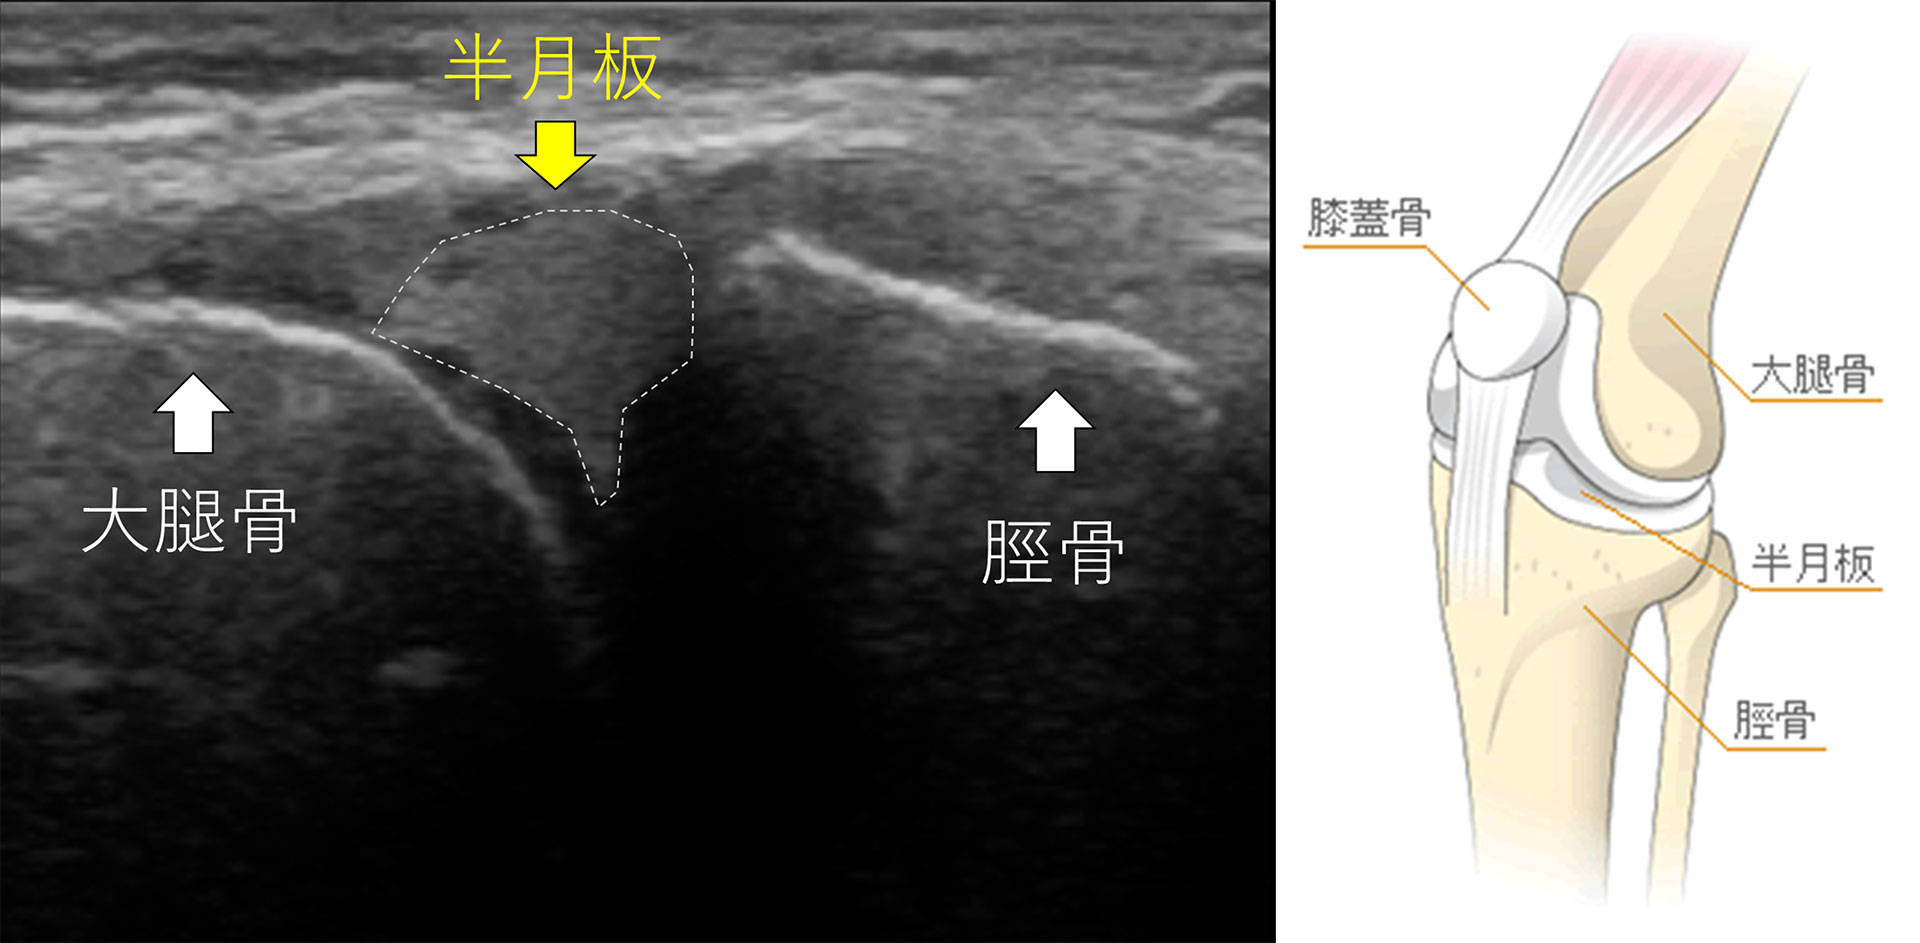

超音波検査(エコー)

当院では、最新の超音波画像診断装置(エコー)を導入しております。骨やじん帯、筋肉まで細かく検査することができ、損傷の程度が正確に観察できます。レントゲン検査と違い放射線を浴びることがなく安全で無害なため、経過観察のために繰り返し検査する事が可能です。

膝半月板のエコー画像

半月板損傷や膝の変形が見れます!